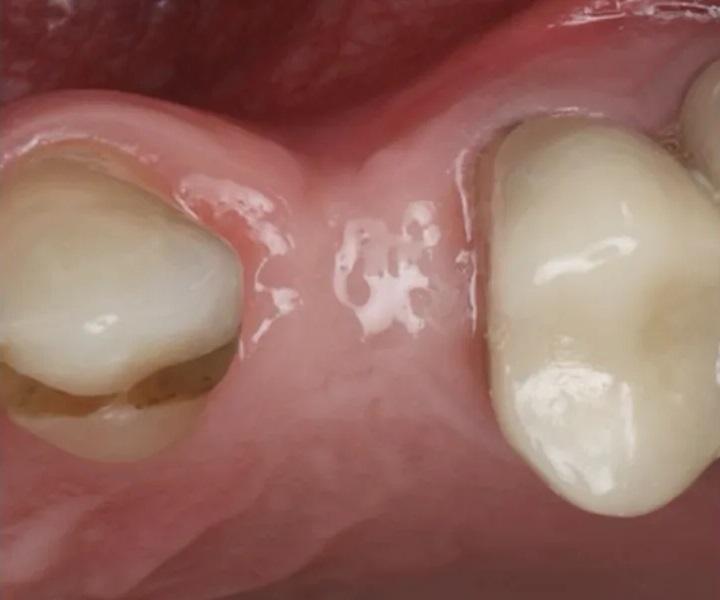

На контрольном осмотре через 16 месяцев клиническая оценка выявила сохраненный объем гребня и стабильную кератинизированную мягкую ткань (Фото 22 и Фото 23). Рентгенологический анализ подтвердил стабильный уровень кости вокруг имплантата № 2.4 и положительные рентгенологические изменения, свидетельствующие о регенерации тканей на медиальной поверхности зуба № 2.5, включая восстановление периодонтальной связки (Фото 24).

Фото 22 и Фото 23. На контрольном осмотре через 16 месяцев: интраоральный окклюзионный вид (Фото 22) и латеральный вестибулярный вид (Фото 23) демонстрируют реставрацию на имплантате с винтовой фиксацией.